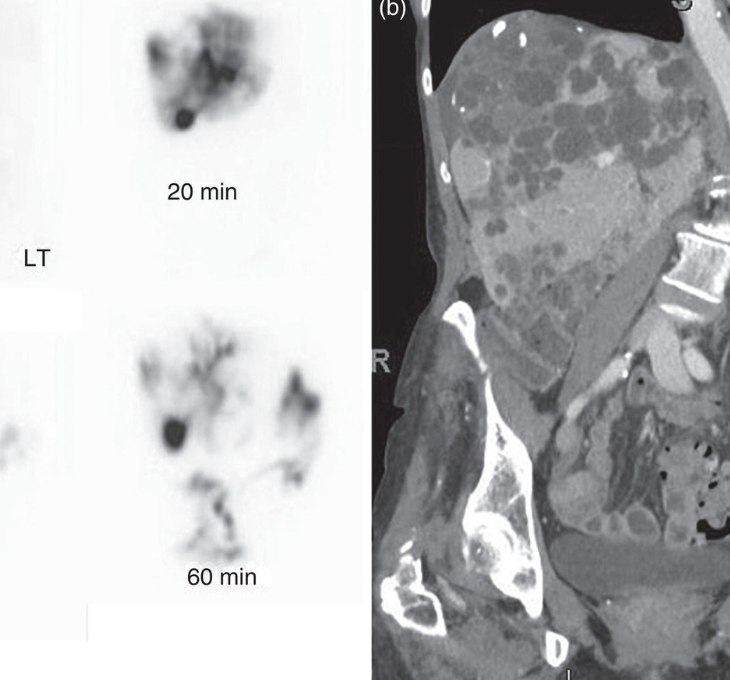

Parathyroid Scan

Used to identify parathyroid gland abnormalities causing elevated calcium levels.